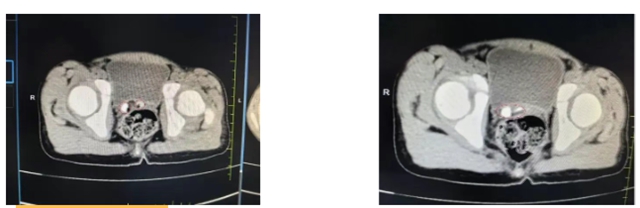

CT显示阴道上段“U”型低密度影